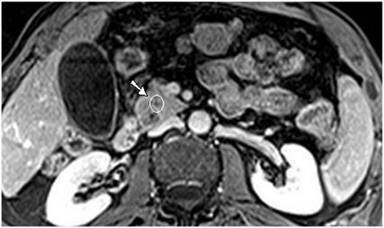

MR imaging was successively performed to evaluate and characterize the nature of the biliary stenosis by acquiring axial and coronal T1- and T2-weighted with/without fat saturation images integrated with MRCP T2-weighted hydro-cholangiographic sequences. In particular, the patient received 900 mL of superparamagnetic oral contrast material (Lumirem®, Guerbet, Paris, France) 20 min before the study. Post-contrast acquisition was performed after the intravenous administration of gadolinium diethylenetriamine pentaacetic acid (DTPA) in a volume of 20 mL with 2 mL/s acquiring T1 fast-field echo short-time inversion recovery (FFE-STIR) images. In particular, cross-sectional T1- and T2-weighted and MR cholangiography sequences showed dilatation of the biliary tree including the intrahepatic ducts, primarily of the left hepatic lobe and the common hepatic duct. Furthermore, MR images showed a lengthy stricture with luminal flow-signal preserved, irregular margins as well as abrupt and asymmetric narrowing in the middle third and intra-pancreatic segment of the common bile duct (Figure 1). A solid lesion along the common bile duct, at same level of the stricture, appearing as circumferential wall-thickening with a firm component projecting into the duct lumen, was also detected (Figure 2); after the administration of contrast medium, the lesion did not show significant enhancement in the arterial phase; however, late-phase images showed non-homogeneous enhancement (Figure 3). There was no evidence of positive lymph nodes or metastatic disease; the characteristics of the MR images were suggestive of a malignant primary stenosis probably by extra-hepatic cholangiocarcinoma. Furthermore, MR views demonstrated mild enlargement of the pancreas associated with a non-homogeneous signal intensity of the pancreatic tissue due to the presence of a hypointense nodule (Figure 3). A second ERCP examination was subsequently performed, which revealed a stricture immediately above and at the level of the intra-pancreatic common bile duct and the biliary stent was removed; brush cytology did not reveal atypical cells and the final report was not indicative of malignancy.

Figure 3. T1-weighted fast-field echo short-time inversion recovery (FFE STIR) post-contrast image shows a solid lesion with inhomogeneous late-phase enhancement (at the level of the intra-pancreatic biliary tract); moreover, MRI demonstrates mild enlargement diffusely involving the head of the pancreas associated with inhomogeneous signal intensity of the pancreatic tissue due to the presence of a hypointense nodule (arrow). |